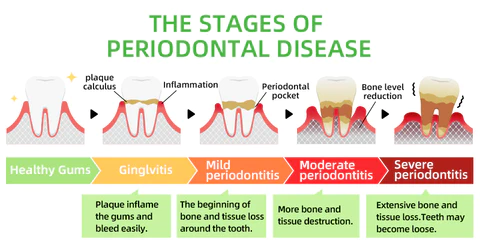

Every day, food residues in our mouths create a breeding ground for various bacteria and microorganisms within the oral cavity. This can result in a range of oral health issues, including bad breath, mouth ulcers, yellow teeth, cavities, calculus buildup, gum inflammation, bleeding gums, tooth sensitivity, weakened or missing teeth, swollen gums, toothaches, loose teeth, tooth loss, and even the risk of oral cancer.

As these conditions worsen, you may experience persistent bad breath, gum inflammation, and other problems. Bacteria continue to harm your gums, leading to issues like bleeding, pain, and redness. Without timely intervention, these oral problems can escalate, potentially causing periodontitis, dental plaque, dental calculus, loose teeth, tooth pain, and eventually tooth loss.

Dental caries develop when germs damage tooth enamel and gradually penetrate into the dentin and even the pulp. This can result in bad breath, toothaches, weakened teeth, and potential tooth loss. The presence of caries often triggers a chain reaction, causing healthy teeth to be affected as germs spread to adjacent teeth.